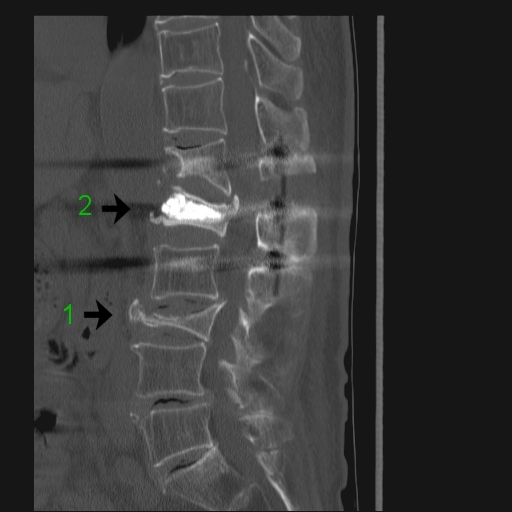

術前術後のレントゲン以下、レントゲン写真を紹介します。「1→」第3腰椎でしょうか、つぶれています。しかし、担当医によればこの部分からの痛みはないようです。 「2→」第1腰椎でしょうか、腹側がささくれています。 又、写真には写っていませんがこの部分の「腰神経叢」滞りがあるようです。 ![]() チタン製のスクリューと固定版を背中側から撮った映像です。 MRで胴体部分を輪切りにした映像です。 縦に3本のスクリューが入れられているのが鮮明に表示されています。 「3→」の部分は避けていた腰椎に人口骨を入れ補強・修正した部分をなります。